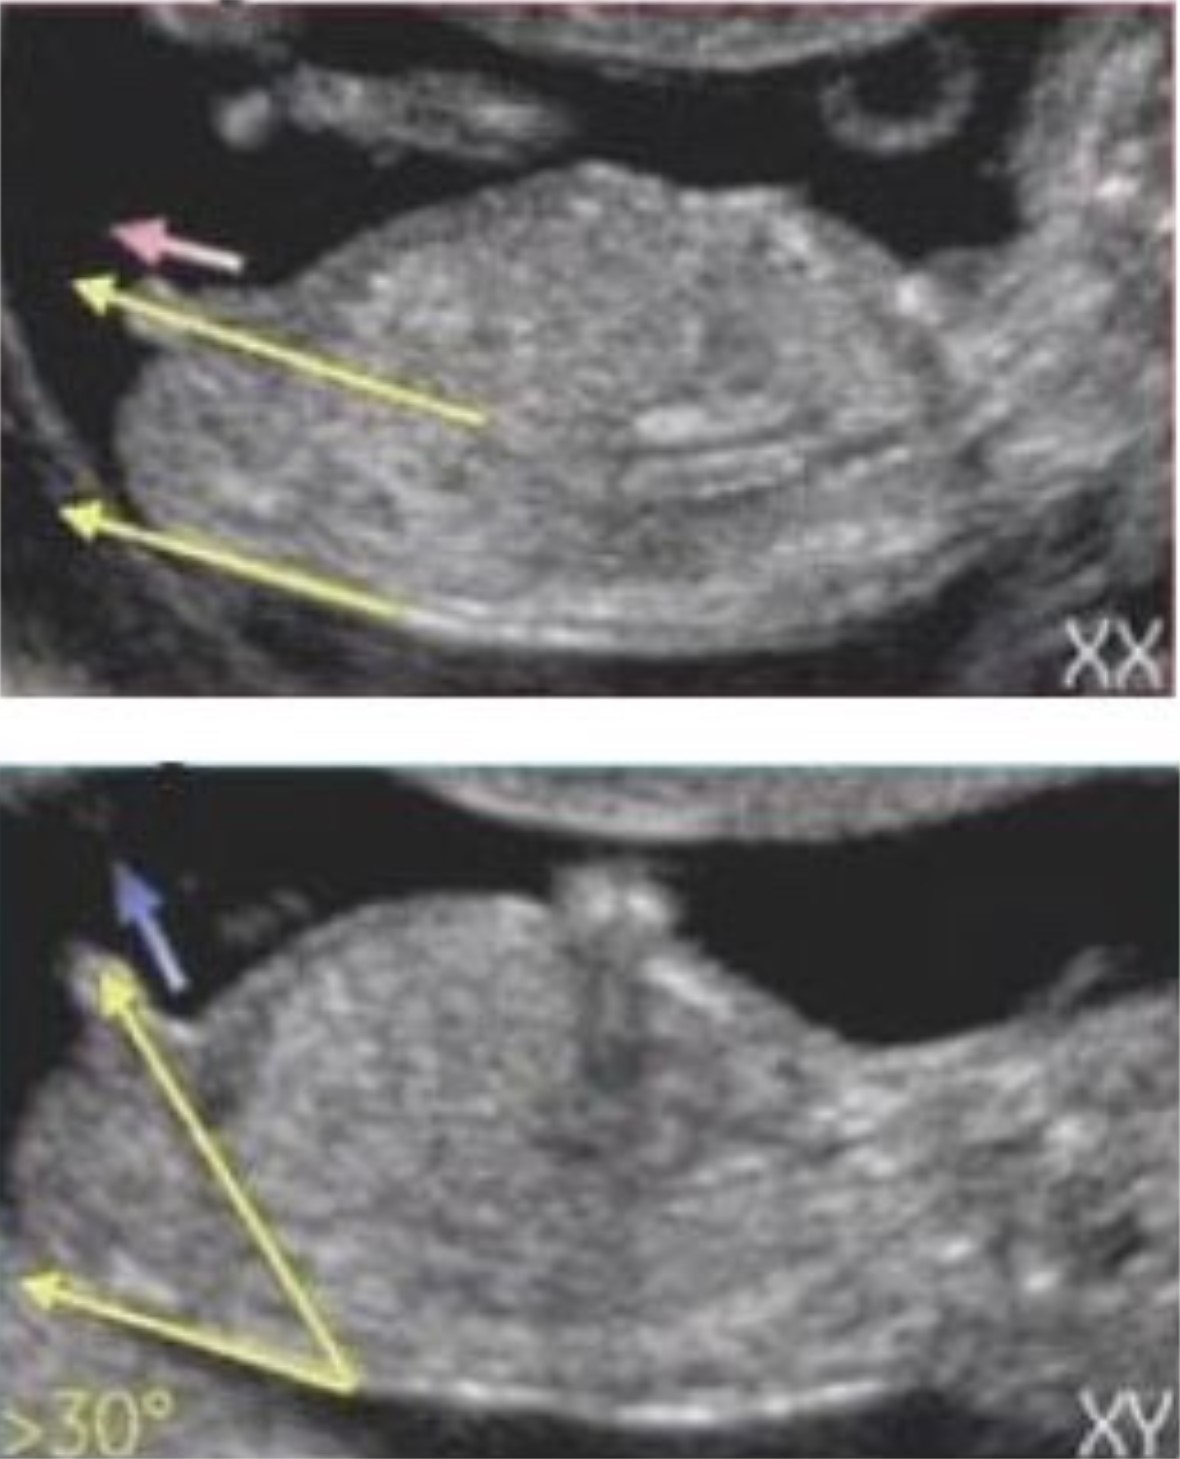

태아 초음파에서 옆모습의 척추와 성기의 각도를 통해 볼 수 있는 방법을 12주 각도법이라고 부릅니다. 12주보다 좀 더 이르면 애매할 수도 있고, 12주가 지나면 성기의 형태로도 추정할 수 있기 때문에 가장 빠르게 성별을 확인할 수 있는 방법입니다. 툭 튀어나온 부위가 척추와 평행을 이루고 있다면 딸, 30도정도의 각도를 이루고 있다면 아들이라고 합니다. 16주 이상 됬을 때 정확한 성별을 판단하기 이전에 가장 정확하게 확인 할 수 있는 방법입니다.

장꾸맘님의 주변 적중률은 100%였고, 인터넷상으로 돌아다니는 적중률도 99%는 되는듯합니다. 일단, 확실할 경우에는 딸에 한표요! 아들에 한표요! 라고 말씀해 주시고, 정말 안보이시는 동영상의 경우 업로드 재요청을 해주시거나, 조건부로 잘 보이지 않는 동영상이지만, 혹은 조심스럽게, ~에 한표요 라고 얘기해 주신답니다. 저의 경우에는 12주2일차 동영상을 올렸고 단답으로 딸에 한표요! 라고 답변해 주셨답니다.

처음말씀드린 바와 같이 16주~20주가 되면 아이의 성별은 병원에서도 확인 가능합니다.(일부 병원은 성별에 대한 언급은 안 해준다고 합니다.) 제가 테스트했던 4가지 방법 중 난황을 제외하고는 딸로 모두 적중했습니다. 16주가 되었을 때 아래 사진과 같이 남아와 여아의 성기가 변화되기 때문에 엉덩이 사진만으로도 성별 확인이 가능하답니다.